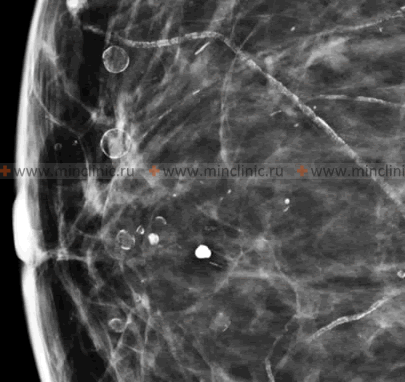

Breast Cysts

Formation and Characteristics

A breast cyst is a common benign, fluid-filled sac that develops within the breast tissue, bounded by a connective tissue capsule. Breast cysts are a frequent manifestation of fibrocystic breast changes (mastopathy), occurring in both nodular and diffuse forms.

A breast cyst typically forms as a result of the dilation (expansion) of one of the breast ducts or lobules. Subsequent accumulation of fluid (secretions) within this dilated space, coupled with the formation of a fibrous capsule around it, leads to the cyst. The fluid within simple cysts is usually clear or straw-colored.

Breast cysts can vary in shape, being round, oval, or sometimes irregular. Their size can range from a few millimeters (microcysts, often not palpable) to 5 centimeters or more in diameter (giant cysts, easily palpable). On ultrasound, a typical simple breast cyst is characterized by smooth, even inner walls and an anechoic (fluid-filled) appearance.

An atypical or complex breast cyst may have internal septations, thickened walls, or intracystic growths (papillary projections) on its walls that protrude into the cyst cavity. These features may warrant further investigation (e.g., aspiration, biopsy) to rule out malignancy, although most are still benign.

Breast cysts can occur as single lesions or, more commonly, as multiple cysts (polycystic changes). In cases of polycystic mammary glands, numerous cysts of different sizes can merge and form multi-chambered clusters. As a result, the altered cystic tissue can occupy a significant portion (more than half) of the breast tissue and may lead to breast deformation or discomfort. Breast cysts are a fairly common pathology, particularly prevalent in premenopausal women, often in the age range of 35-55 years, and are less common in nulliparous women compared to those who have had children, though they can occur in any woman.